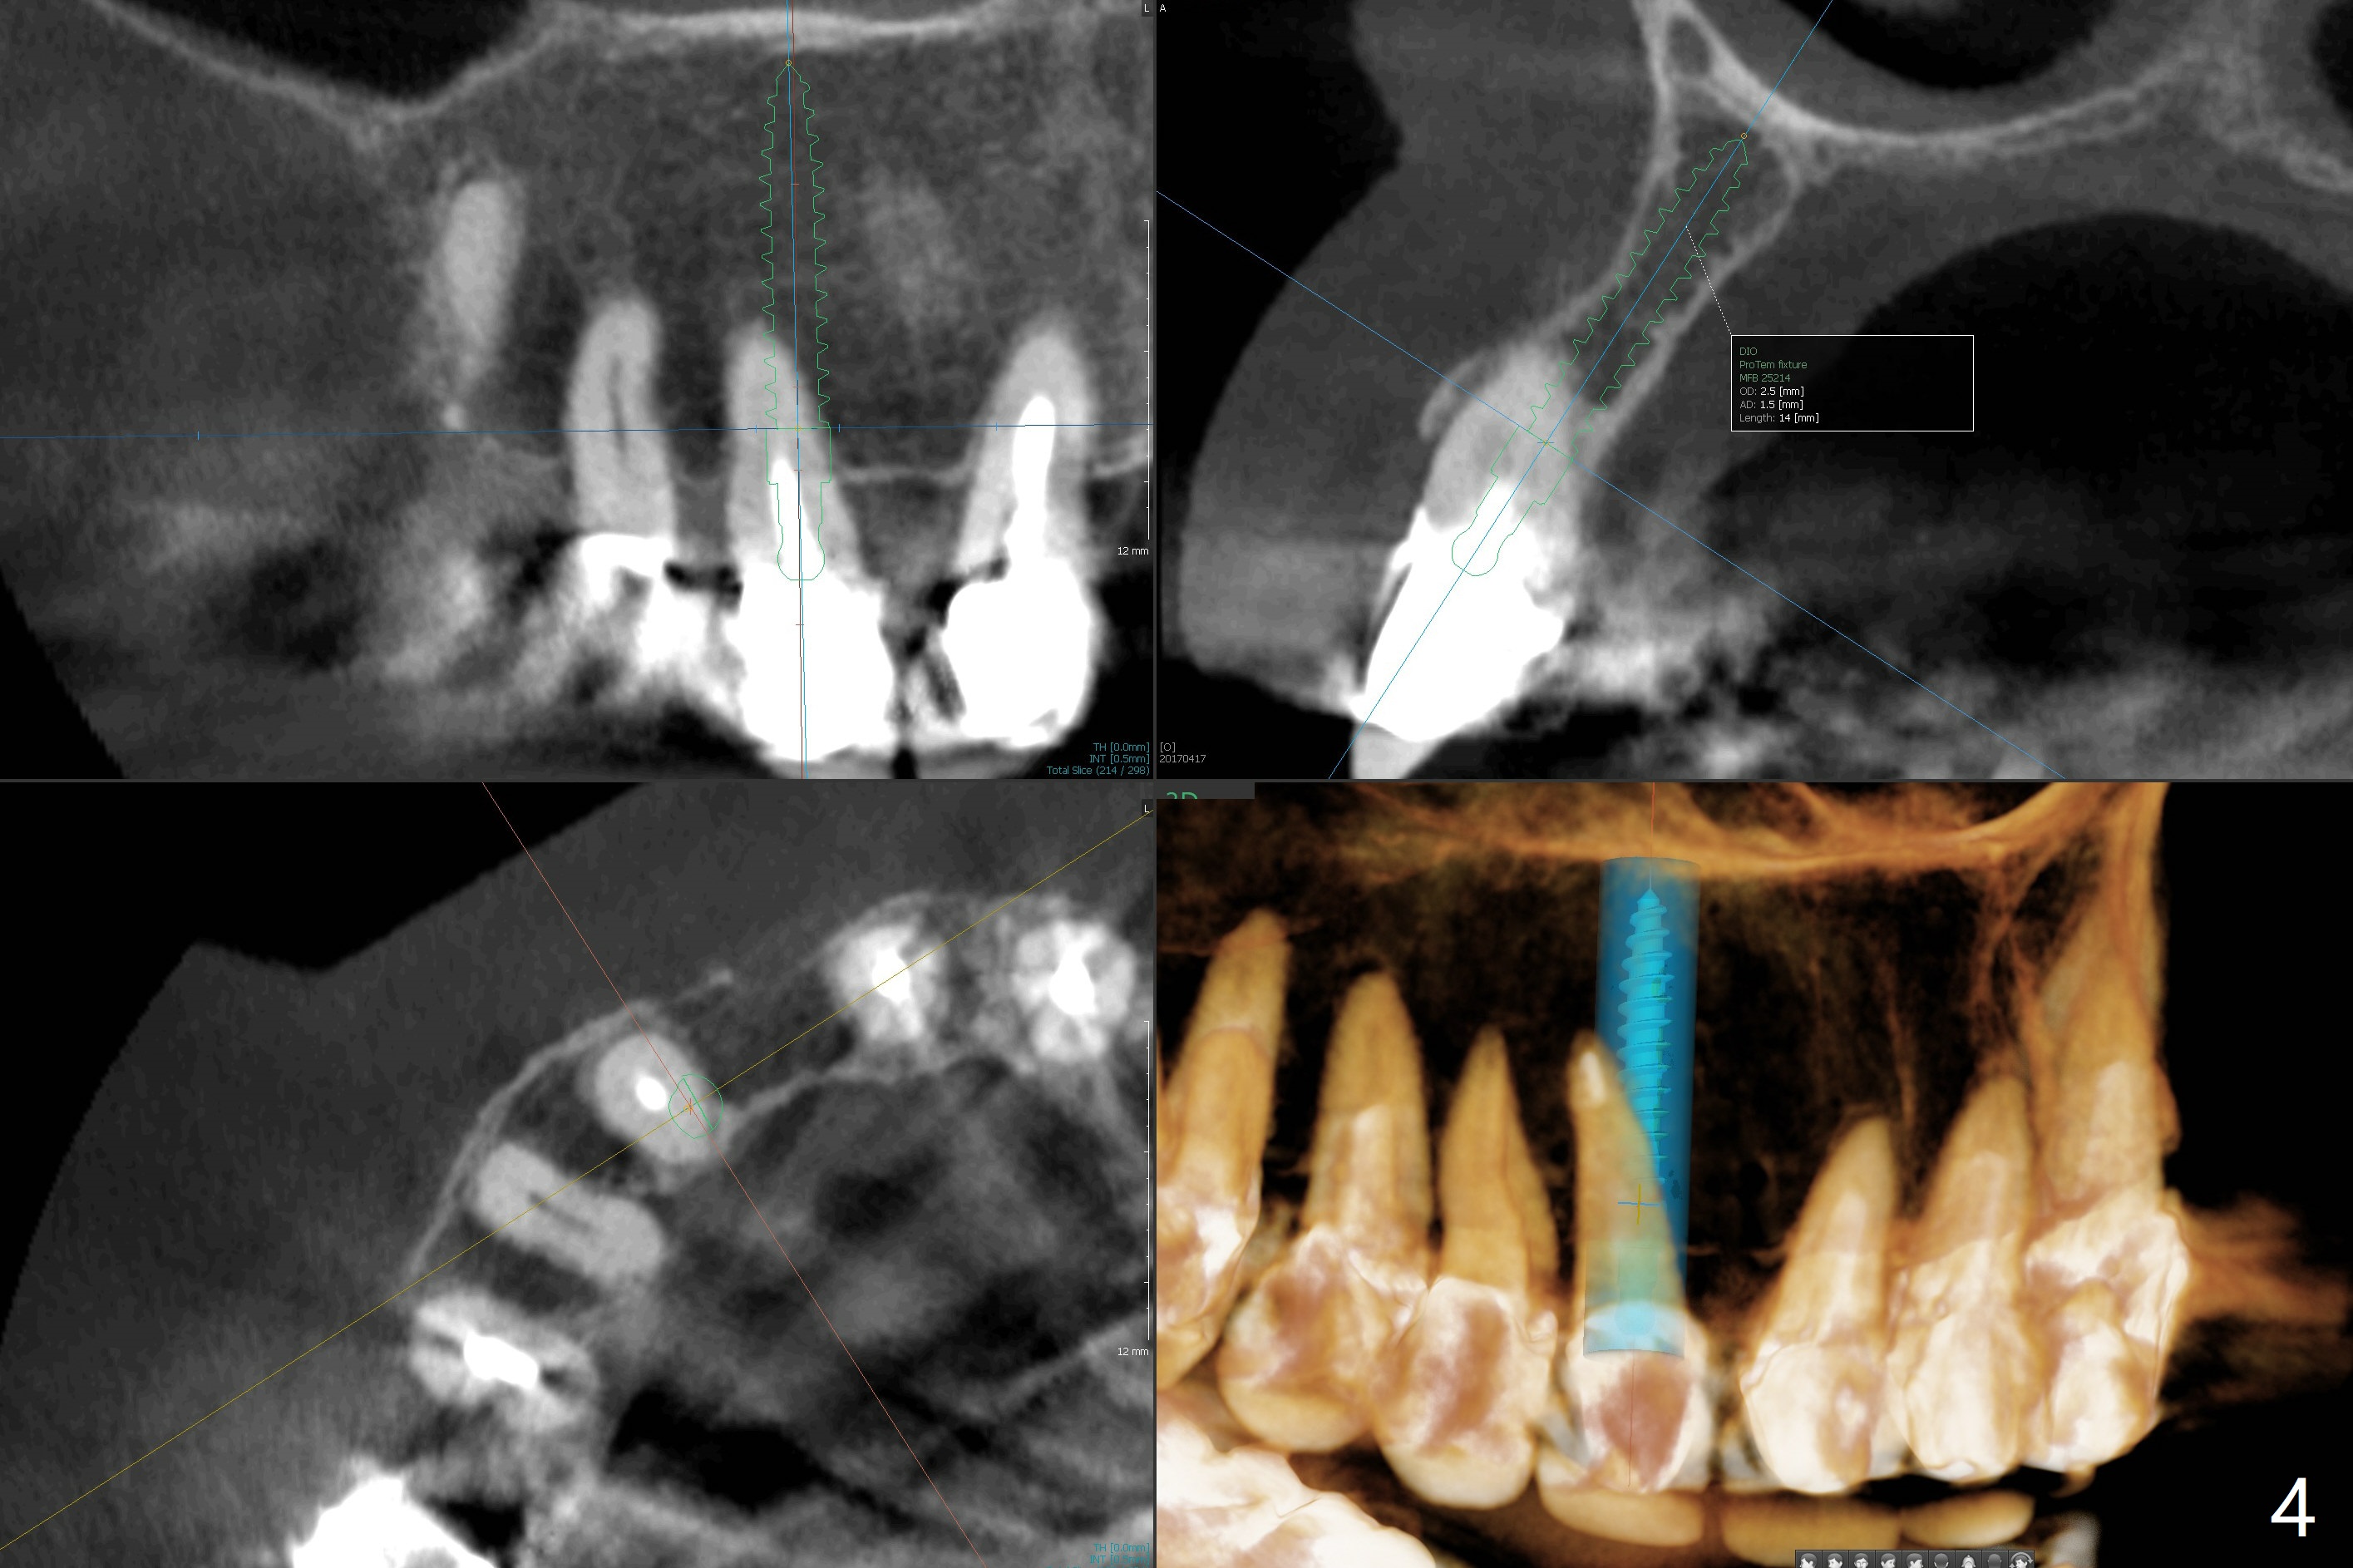

A 67-year-old woman has multiple restoration (difficult for guide preparation). The tooth #6 fractures equigingival with a separated file (Fig.1 <). Because of missing #7, the gingival embrasure between #6 and 8 is large (*). To reduce it, the mesial crest will be trimmed by using 6 mm profile drill after placement of a 3.5x13 mm FC implant (low bone density) and a narrow temporary abutment is going to be used to squeeze the papilla coronally and mesially. In a coronal section, osteotomy will be initiated in the middle of the palatal slope of the socket (Fig.2). A 4 mm x15 degree ~3 mm cuff angled abutment may be used before impression. Take preop photos to show the large gingival embrasure between #6 and 8. The other way to reduce the gingival embrasure is to place an implant mesially. It appears that a 3.5 mm implant is too large for the mesial ridge (Fig.3), while a 2.5 mm one is proper (Fig.4,5).